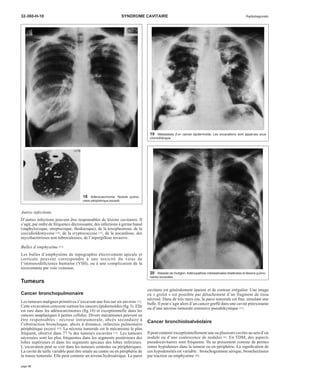

1 Tuberculose pulmonaire post-primaire.

A. Opacités hétérogènes du som-met

droit dont la cavitation est dif-ficile

à affirmer.

B. Une petite cavité est évidente

sur l’examen tomodensitomé-trique.

B